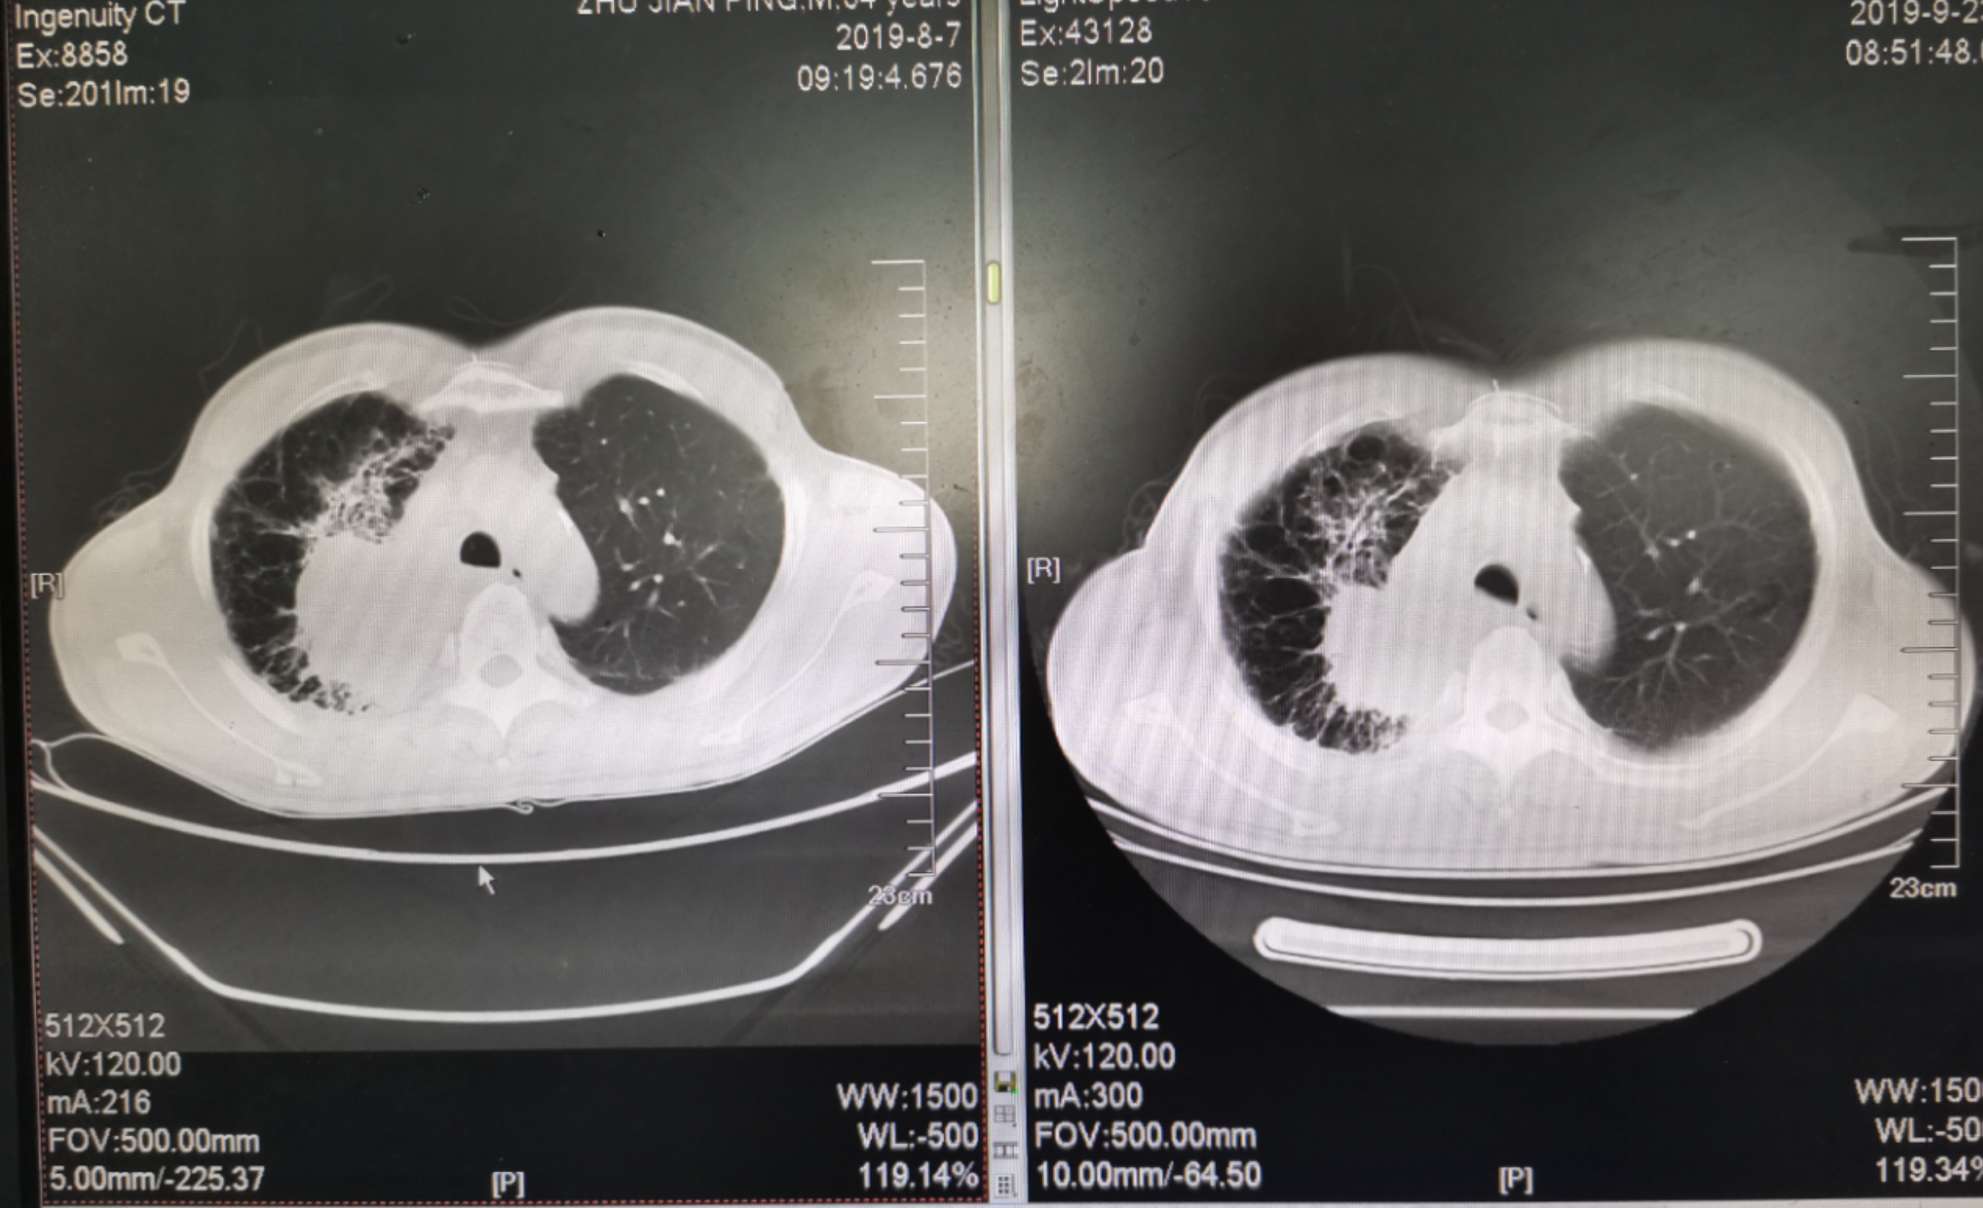

二化联合一k后复查ct对比

左边是上月化疗前的,右边是昨天拍的,今天上了第二次k药,准备明天第三期化疗。

我自己对着拍的,切面对的不是很准确,但大致上看的出来明显小了。